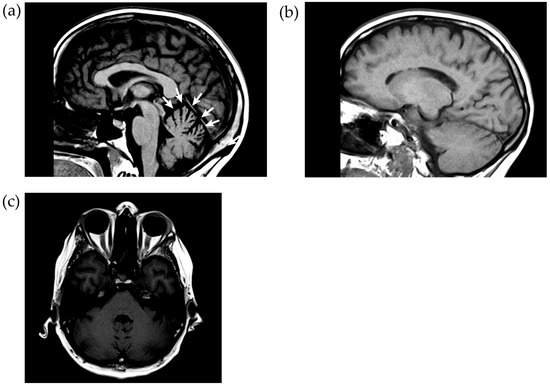

3.5. Imaging